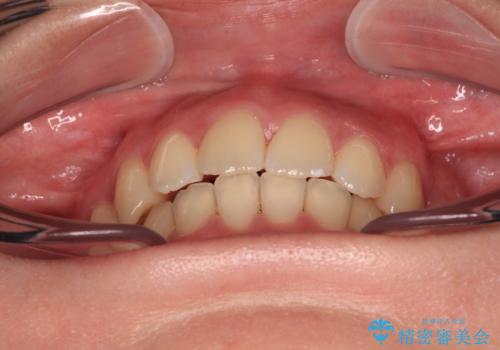

- 前歯のデコボコと突出感を気にして来院された患者様です。

上下左右第一小臼歯4本を抜歯して、積極的に口元を引っ込めるよう、ワイヤー装置にて矯正治療を行うこととしました。

口の閉じにくさが改善され、横顔のシルエットも大幅に改善されました。